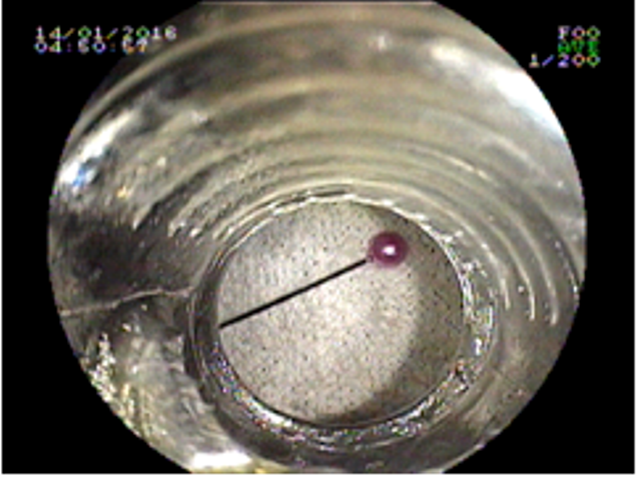

Do bất cẩn, bé gái nuốt phải kim thêu vào bụng nên đau dữ dội và được gia đình chuyển từ Cà Mau lên Cần Thơ cấp cứu.